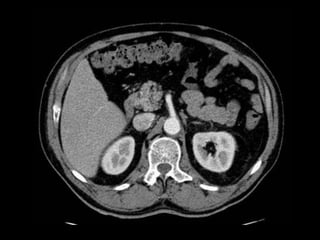

• TAC: Permite identificar los músculos que constituyen

la pared abdominal anterior y el transverso del

abdomen, así como el contenido del saco herniario

Diagnóstico

• Dolor en relación con el desgarro de los

tejidos y con la frecuente epiploitis

acompañante

• EF

• TAC